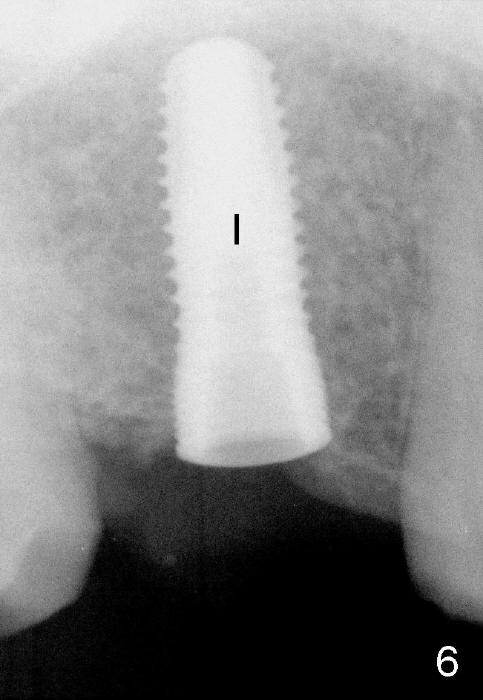

A 5.3x14 mm submerged implant (Fig.6 I) is placed with insertion torque >35 Ncm. There is minimal bone resorption at the crest 3 months postop (Fig.10 (H: healing abutment), Fig.11 (A: cemented abutment: 6.8x4(2) mm)). Nine months post cementation (12 months postop), bone resorption at the crest remains minimal (Fig.12). Bone loss appears not to get worse 22 months post cementation (Fig.14). Xin Wei, DDS, PhD, MS 1st edition 08/07/2014, last revision 06/16/2018 |